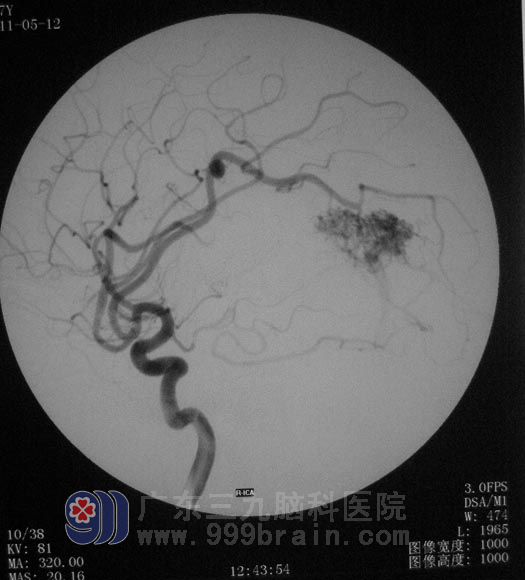

行全脑血管造影检查,结果显示:右颞枕动静脉畸形,约3cm×4cm大小,畸形血管团有三条动脉供血,主要为右侧大脑中动脉分支的供血。经过反复讨论及仔细地斟酌,鲁明主任为杨老师制定下治疗方案:先行部分畸形血管栓塞,再根据栓塞后情况行开颅切除没有完全栓塞的畸形血管。

▲栓塞后